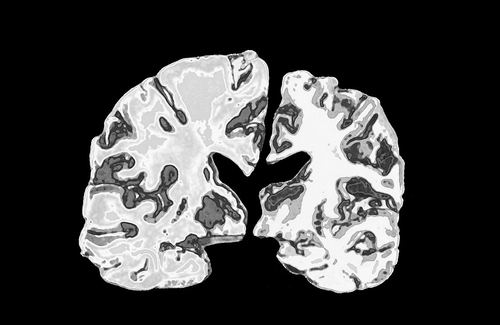

正常人大腦切片(左)與阿爾茨海默病患者大腦切片的對比。圖片來源:Jessica Wilson

該研究通過對人類腦組織的分析和一系列小鼠實驗,揭示了一個共性模式:大腦中的鋰濃度下降往往伴隨著記憶的喪失,而阿爾茨海默病的神經病學標志物,即淀粉樣斑塊和tau蛋白纏結,也會同步出現。研究人員同時在小鼠中發現,有證據表明一種特定類型的鋰補充劑可以逆轉這些神經學變化,恢復喪失的記憶,使大腦重回更年輕、更健康的狀態。

研究人員發現,在人類大腦中,受阿爾茨海默病影響區域的鋰元素水平低于未受影響的區域。而在患有輕度認知障礙的人群中,大腦中的鋰被“困”在淀粉樣斑塊里,導致可用于基本大腦功能的鋰減少。Yankner表示,這種鋰的缺失“隨著病情進展而越發嚴重”。